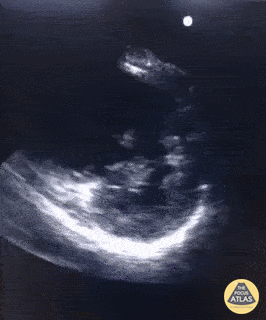

Right Ventricular Dysfunction - The D-Sign in Acute PE

A 70 year old female patient presented with complaints of acute dyspnea. Oxygen saturation was 86% on room-air improved with O2-supplementation. She had poor hemodynamics with SBP ~ 100 mmHg. POCUS showed obvious right heart strain with a D-sign and thrombus intermittently visualized in the right ventricle. Correct therapy (thrombolytics) were given almost straight away after presentation in the ED because POCUS was available. Once stabilized, the patient was taken for a CTA chest which demonstrated a saddle embolism. Dr. Van Roosmalen